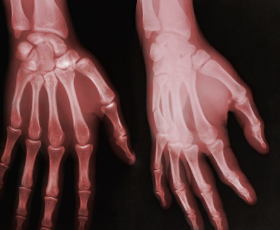

손가락 관절염 초기증상 원인 치료방법

손가락 관절염 초기증상 원인 치료방법 등 정보에 대해 정리해드리도록 하겠습니다. 손가락 관절염은 손가락 마디에 통증이나 염증이 생기는 질환입니다. 손가락 관절염의 원인은 나이가 들면서 관절의 연골이 닳거나, 부상이나 염증으로 인해 관절이 손상되는 경우가 있습니다. 손가락 관절염은 삶의 질을 떨어뜨리고, 일상생활에 불편을 주는 문제입니다.